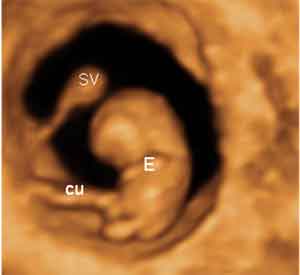

Ecografía en 3D de embarazo de 8,6 semanas.Ecografía 3D. Se aprecia claramente el cordón umbilical (cu), el saco vitelino (SV) con su tallo y el embrión (E) con la cabeza, cuerpo y extremidades sin terminar de completar.